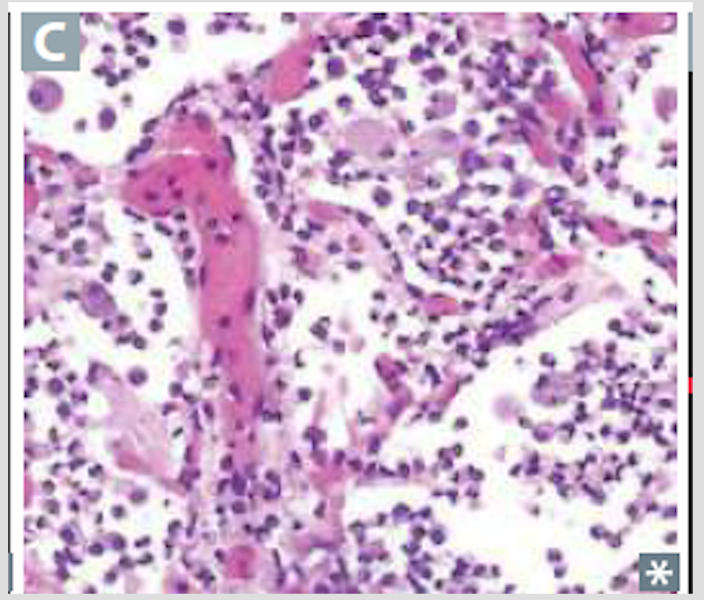

Acute inflammatory infiltrates from bronchioles into adjacent alveoli; patchy distribution involving more that one lobe

Bronchopneumonia